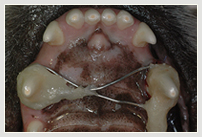

Zahnfraktur des Hundes vor Krone Zahnverletzung mit ¾ Krone im Oberkiefer Kunststoffplombe und im Unterkiefer Krone

Zahnluxation linker Oberkiefer Eckzahn Zahnluxation Behandlung luxierter Zahn wieder in Position